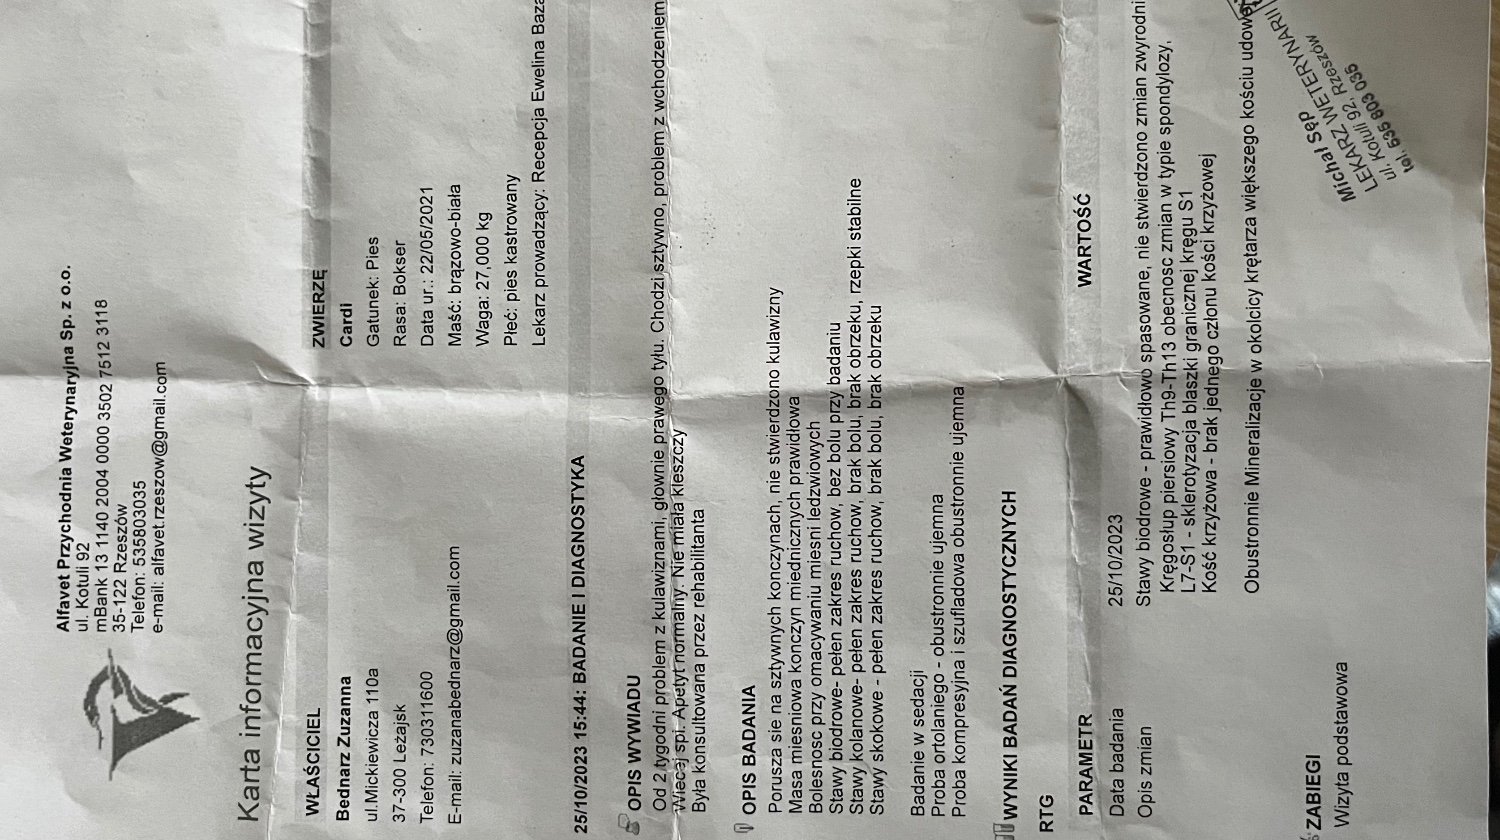

Cardi to młoda suka w typie boksera, ma zaledwie 2,5 roku, od zawsze miała wielkie serce dla ludzi, kocha każdą napotkaną osobę i jest nieodłącznym członkiem naszej rodziny, jednak od paru miesięcy nasza zawsze pełna energii sunia zaczęła mieć mniejsze chęci do zabawy, bieganie stało się dla niej cięższe i jej kondycja się pogorszyła, wtedy myśleliśmy, że to problemy z sercem, jednak na echo nic nie wyszło wiec tłumaczyliśmy sobie, że dorasta. Dokładnie 10.09 zaczęła kuleć na tylną prawą łapę, chodzić o sztywnych nogach, pokazała się również opuchlizna na miednicy, początkowo obstawialiśmy, że coś sobie naderwała, dwa dni później (12.09) pojechaliśmy do fizjoterapeuty, miała robione zabiegi laseroterapii + terapii ultradźwiękami, diagnoza była kierowana w stronę problemów z rzepkami. Na pare dni był spokój jednak kulawizna powróciła, a Cardi zaczęła piszczeć przy wstawaniu czy kładzeniu. Udaliśmy się do ortopedy na zdjęcia rtg i niestety tam wyszło więcej problemów, a dokładniej:

-zmiany w typie spondylozy w kręgosłupie piersiowym Th9-Th13

-sklerotyzacja blaszki granicznej kręgu S1

-brak jednego członu kości krzyżowej

-obustronna mineralizacja w okolicy krętarza większego kości udowej

-mineralizacja w kolanie prawej tylnej łapy

Dodatkowo na płucach widać niepokojące zmiany. Jest podejrzenie nowotworu w kręgosłupie wiec musimy wykonać TK z kontrastem (1800zl), później gdyby wyszła zmiana będziemy robić biopsje. Aktualnie jest na lekach przeciwbólowych, mamy również podawać steryd. Z każdym dniem widać po niej, że jest coraz gorzej, nie ma chęci do wstawania czy zabawy, Cardi potrzebuje kosztownej rehabilitacji, początkowo 8-10 zabiegów (1200-1500zl) dzięki którym ból który odczuwa przy poruszaniu się zmaleje, a postępująca spondyloza spowolni swój przebieg. Psina będzie mogła ponownie cieszyć się życiem bez ciągłego bólu i dyskomfortu który udawało jej się tak dobrze maskować. Jest wyjątkowo silnym psem jednak bez specjalistycznej pomocy i leczenia nie wygra z tą niesprawiedliwą chorobą. Nie chcemy się poddawać, nasza Cardi dopiero co zaczęła swoją przygodę, jeszcze nie nadszedł jej czas.